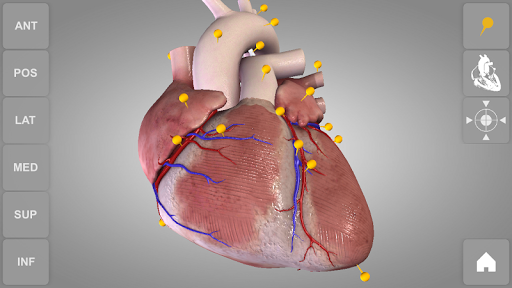

Heart 3D Atlas of Anatomy allows you to rotate a highly realistic 3D heart model as it was in your hands.

The human heart anatomical 3D model is revolvable in any direction giving a 360° view of the object.

User can choose external view or section view. Moreover, the names of specific anatomical areas can be shown touching the related pins (available in the full version only).